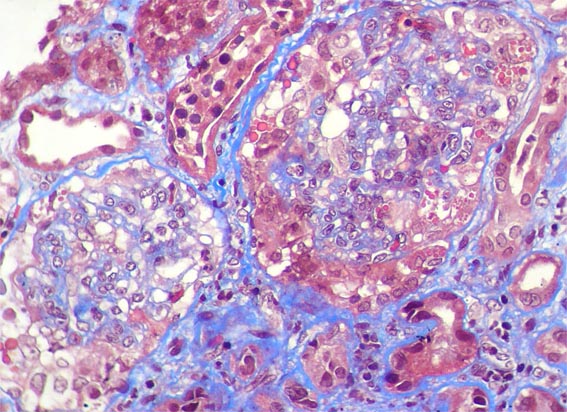

Figure 4.

Masson's

trichrome stain,

X400.